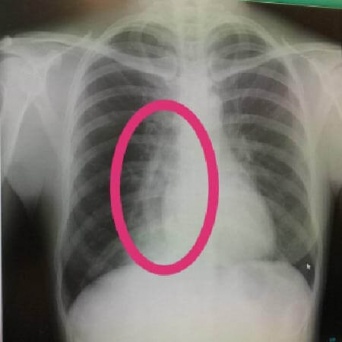

写真はイメージ